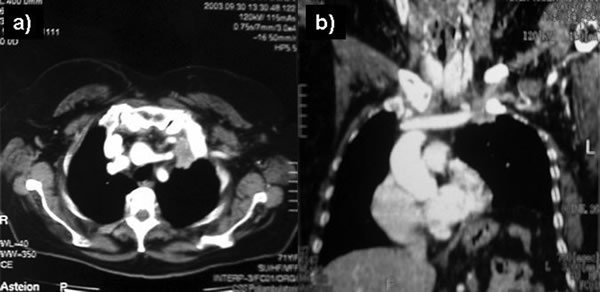

The anterior transcervical thoracic approach described by Dartevelle [15] or as modified by Grunenwald [16] should be added when the apical tumor involves the subclavian vein (Figure 12) that can be closed or replaced in the invaded segment and reconstructed using a reinforced PTFE graft (Figure 13). With anterior extension of the cancer from the apex downward to the innominate vein or superior vena cava (Figure 14), the anterior approach proposed by Masaoka [17] may offer a good exposure for surgery (Figures 15-16).